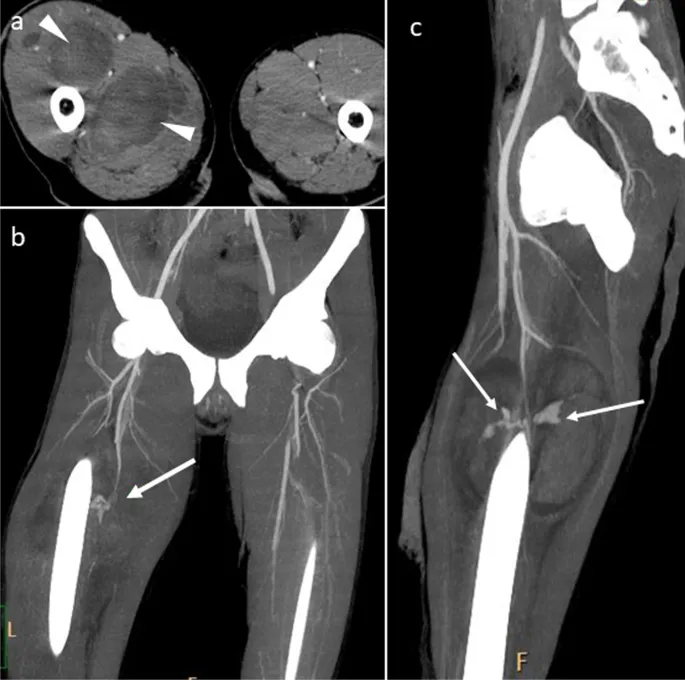

- CT Angiography (CTA): Modality of choice for stable patients. High sensitivity & specificity.

⭐ CTA is the gold standard for diagnosing hemodynamically stable patients with suspected peripheral vascular trauma, offering detailed anatomical information.

- Endovascular Management (selected cases): Covered stents for pseudoaneurysms/fistulas; embolization for non-critical vessel bleeding.

- Pseudoaneurysm, Arteriovenous Fistula (AVF)